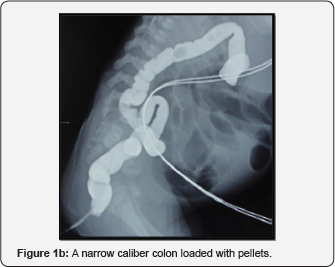

A full term baby girl weighing 2500 grams, delivered by a lower segment caesarean section presented with a cystic swelling in the lower back on her first day of life. The baby had already passed urine and meconium. The antenatal, perinatal and postnatal history was unremarkable. Clinically the child was diagnosed as a case of lumbosacral MMC without any neurological deficits or hydrocephalus. This was confirmed by an ultrasound of the spine and cranium. The child underwent excision of the MMC with laminotomy and detethering of the cord and she had an uneventful immediate postoperative period. Child could not be breast fed postoperatively as her mother was admitted at a peripheral hospital post caesarean section delivery, so formula feeds (Lactodex) were started from the second postoperative day. On the fourth postoperative day the child developed intolerance to feeds with bilious vomiting, abdominal distension and constipation. Preoperatively the child had passed meconium on day one of life and had normal stool habits. A radiograph showed dilated small bowel loops and paucity of bowel gas in the central and right lower quadrant (Figure 1a & Figure 1b).

A diagnosis of neonatal intestinal obstruction was made and the child was managed conservatively for 24 hours. NEC was unlikely as the baby was full term, appropriate for gestational age and the sepsis screen was negative. A contrast enema ruled out atresia but it showed a microcolon loaded with pellets. Since the child did not decompress with repeated attempts of enema and had progressively increasing abdominal distension, emergency exploratory laparotomy was planned.